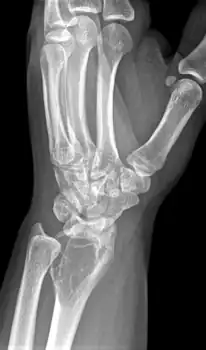

X-ray of a giant-cell bone tumor in the head of the fourth metacarpal of the left hand

Imaging

On X-ray, giant-cell tumors (GCTs) are lytic/lucent lesions that have an epiphyseal location and grow to the articular surface of the involved bone.[11] Radiologically the tumors may show characteristic 'soap bubble' appearance.[12] They are distinguishable from other bony tumors in that GCTs usually have a nonsclerotic and sharply defined border. About 5% of giant-cell tumors metastasize, usually to a lung, which may be benign metastasis,[13] when the diagnosis of giant-cell tumor is suspected, a chest X-ray or computed tomography may be needed. MRI can be used to assess intramedullary and soft tissue extension.